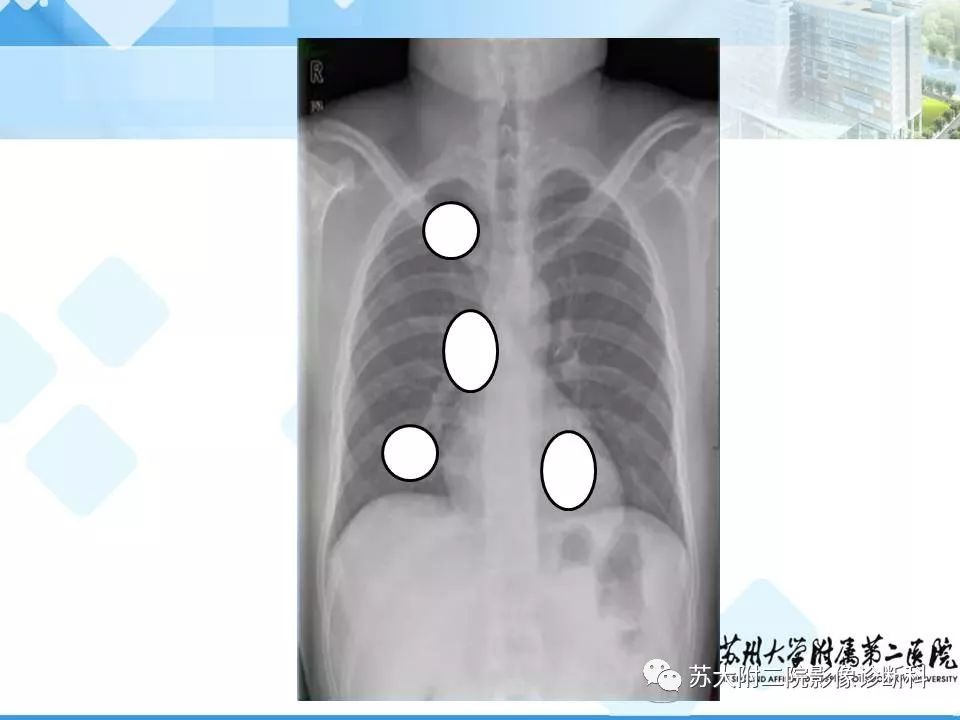

胸部X线平片的漏诊陷阱